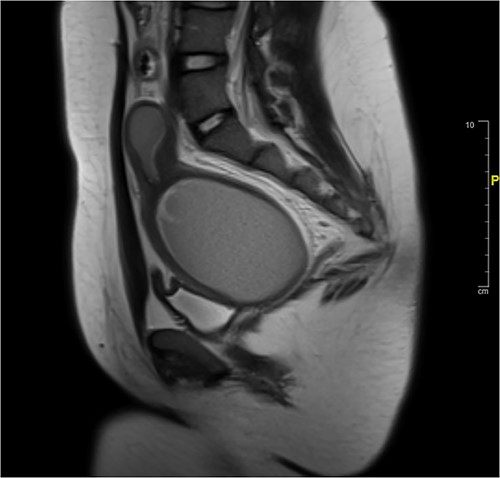

A 13-year-old female presented to the emergency department for increasingly severe chronic cyclic abdominal. She reported thelarche and pubarche at age 11 but had not reached menarche. Physical exam was significant for general abdominal tenderness and firm abdominal mass. External genitalia were notable for a normal hymen but no vaginal opening or bulge. On rectal exam, a firm mass was palpated ~4 cm proximal to anal opening. Imaging confirmed HMC with distension of the proximal vagina measuring 9.9 cm in its greatest dimension. The area of vaginal agenesis was ~5 cm from distal end of HMC to the perineum (Fig. 1).

Pre-vaginoplasty MRI- Image was taken after IR drainage and suppression to allow distension pre-vaginoplasty.